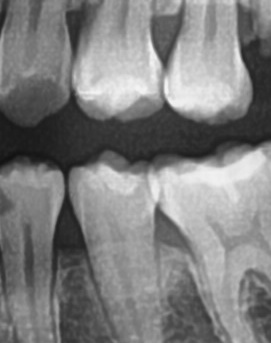

어금니 뒤 잇몸 부음 우선 원인부터 살펴보면 이러한 증상은 단순한 잇몸 염증에서부터 더 심각한 치주 질환이나 사랑니 문제까지 다양하게 발생할 수 있는데요. 보통 잇몸이 붓는 것은 세균 감염, 음식물 잔여물에 의한 자극, 치주 질환, 사랑니 문제 등이 원인이 되는 경우가 많으며 증상이 가벼울 때는 자연적으로 가라앉을 수도 있지만, 제대로 치료하지 않고 반복되는 잇몸 문제가 갈수록 진행된다면 염증이 심해지고 통증이 심해질 수 있고 잇몸이 주저 앉거나 심한 경우 치아가 흔들릴 수 있어서 원인을 정확하게 파악하고 적절한 치료를 받는 것이 중요하다고 볼 수 있어요

좀더 자세히 원인과 증상에 대해 살펴보면 어금니 뒤쪽은 치아 구조상 칫솔이 잘 닿지 않는 부위라서 음식물 찌꺼기가 남아 있거나 플라그가 쉽게 쌓이게 되는데 치아 사이 공간이 좁고 잇몸이 연약한 부분이라서 세균이 번식하기 쉬운 환경이 만들어지고, 이로 인해 잇몸이 붓거나 염증이 생길 가능성이 커질 수 있었어요

처음에는 가볍게 붓고 불편한 정도지만, 점점 심해지면 통증이 발생하거나, 잇몸이 붉어지고 단단해지면서 눌렀을 때 고름이 나오는 경우도 있어요. 이런 경우 단순한 염증이 아니라 치주염으로 발전할 가능성이 있기 때문에 치과에서 정확한 검진을 받는 것이 필요한 거예요

가장 주의해야 하는 문제 중에 치주염이 진행되면 어금니 뒤쪽뿐만 아니라 전체적인 잇몸이 약해질 수 있어요. 치주염은 치아를 둘러싸고 있는 조직이 손상되는 질환인데 특히 잇몸이 자주 붓거나 피가 나는 경우에는 치주염이 진행되고 있는 신호일 수 있기 때문에 단순한 잇몸 붓기로 넘기지 않는 것이 좋으며 치료를 받지 않으면 결국 치아를 지탱하는 뼈가 약해지고, 심한 경우에는 치아가 흔들리거나 빠질 수도 있었어요.